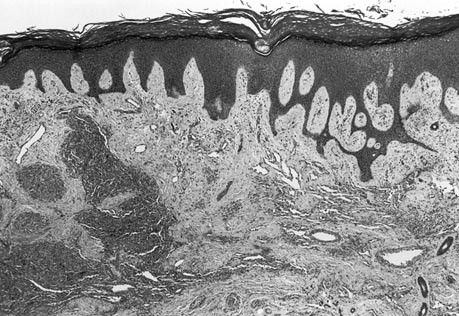

In all five patients, the important microscopic features leading to the diagnosis included the tumor hypercellularity, the spindle cells growing in sheets and nodules or large confluent vascular masses focally with a “cannon-ball” pattern (Fig. 3), and the spindled tumor cells exhibiting the vasoformative slit-like lumen, reminiscent of Kaposi’s sarcoma (Fig. 4). In Cases 1 and 2, tumor nodules were sparse in the dermis, but were distributed extensively in the subcutis. Bone involvement was observed in Cases 1 and 4. Focal broad fibrosis dividing the cellular tumor was most prominent in Patients 1, 2, and 4, but inconspicuous in the others. Similarly lymphangiomatosis was prominent in Cases 3 and 5, but inconspicuous or absent in the other patients (Fig. 5). Apart from the Kaposi-like areas with microhemorrhages, elsewhere the tumor cell exhibited distinctly gaped and rounded vascular lumen. In Patient 5, who received a course of interferon followed by Chinese herbal medicine for 5 years before amputation, the typical tumor nodules were only few on microscopy. In this case, most of the remaining skin, deep soft tissue, and bone showed hyalinized stroma with heavy hemosiderin deposition and collapsed small vessels, reminiscent of regressed tufted angioma (Fig. 6). The tumor also involved a few axillary lymph nodes in Patient 1 (11). For all cases, the tumor cells showed immunoreactivity to vimentin, C31, CD34, and UEA-1 lectin, but variable or equivocal staining for Factor VIII. In Cases 1 and 2, the tumor was completely removed by surgery, while most of the tumor remained in the other patients.

The cutaneous appearance of KH is generally not distinctive, apart from the extensive “port wine” hemangiomatous presentation. The diagnosis rests on the histology, and on its correlation with clinical features, in particular the depth of the lesion. The vasoformative spindle cells with slit-like lumen, microhemorrhages, and fascicular arrangement constitute its unmistakable resemblance to Kaposi’s sarcoma (17). However, all five patients also showed a gaped vascular lumen, large coalescent nodules, broad fibrosis with scanty inflammatory cells, deep extension to soft tissue and bone, which all set them apart from Kaposi’s sarcoma (13, 16, 17). The irregular tumor masses with uncanalized spindle cells distinguish KH from solitary juvenile hemangioma, cellular hemangioma of infancy, and multiple hemangiomas (16, 17). Spindle cell hemangioendothelioma is a small skin lesion with focal resemblance to KH, but also features cavernous spaces, thrombosis, and calcospherules not seen in KH (11, 17). Angiosarcoma differs from KH by the pleomorphic and mitotically active tumor cells (17).